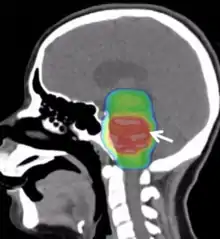

Radiotherapy

Conventional radiotherapy, limited to the involved area of tumour, is the mainstay of treatment for DIPG. A total radiation dosage ranging from 5400 to 6000 cGy, administered in daily fractions of 150 to 200 cGy over 6 weeks, is standard. Hyperfractionated (twice-daily) radiotherapy was used previously to deliver higher radiation dosages, but did not lead to improved survival. Radiosurgery (e.g., gamma knife or cyberknife) has a role in the treatment of DIPG and may be considered in selected cases.